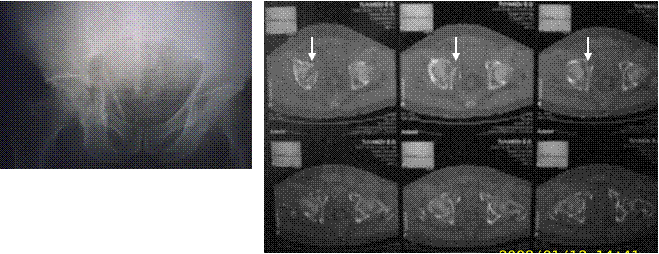

Компьютерная томография (КТ) таза после оценки рентгеновских снимков в большинстве случаев помогает еще более точно определить расположение линий перелома, особенно – при повреждениях вертлужной впадины (рис.9). Целостную картину перелома создает объемная трехмерная реконструкция. С целью детализации повреждений мягкого остова таза и его сочленений можно использовать МРТ или сцинтиграфию.

Рис.9. Перелом дна вертлужной впадины со смещением отломков: рентгенография и компьютерная томография.